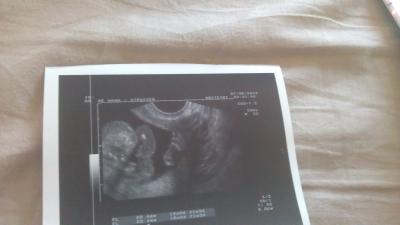

Hallo Ihr lieben, ich war heute beim FA. Alles in Ordnung das kind ist jetzt insgesamt 17 cm groß von Kopf bis Fuß. Und wir wissen was es wird, es wird eine kleine Prinzessin...... Alles super, Werte sind auch top, hänge euch mal ein Bild mit ran. Heute wollte es nicht fotografiert werden also hat der liebe Fa den Fuß aufgenommen. sieht man ganz Rechts.......

Bild zu Zurück vom Fa mit Outing - Forum für November - Mamis